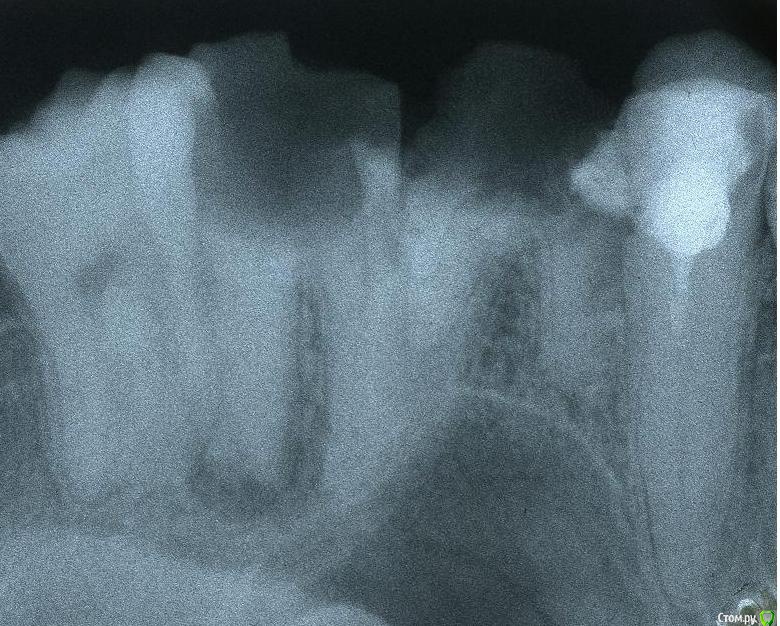

stomt Опубликовано 17 июля, 2017 Поделиться Опубликовано 17 июля, 2017 Вот есть снимок правого верхнего зуба (7-ки). Там очевидна бифуркация, и гной. Только непонятно -- под самим корнем или посредине тоже. Хотелось бы услышать варианты лечение зуба, хотя понятно что это трудный случай -- но просто удалить не могу себе позволить.Бифуркация кажется до самого верха не дошла пока-что. Ссылка на комментарий

Stomart Опубликовано 17 июля, 2017 Поделиться Опубликовано 17 июля, 2017 Вы наверно имеете ввиду "перфорация"? Снимок плохого качества, не видно ничего. Ссылка на комментарий

stomt Опубликовано 17 июля, 2017 Автор Поделиться Опубликовано 17 июля, 2017 Я не специалист -- потому термин "перфорация" не утреблял -- хотя насколько понял это когда уже сеть дырка (в этом случае) от процеса бифуркации.Про бифуркацию мне сами врачи сказали -- однако темная вертикальная полоса -- это гной, часть гранулемы? Просто следствие бифуркации, очевидно, это не есть.Касательно качества снимка -- оно должно быть хорошого качества, ибо в предыдущем снимке, было явное накладывание изображений (потому я специально его переделывал). Ссылка на комментарий